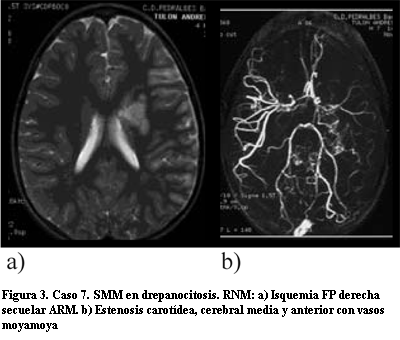

La TAC o la RM craneal inicial en diecisiete casos evidenció zonas de isquemia: nueve fueron isquemias agudas, cuatro agudas y secuelares y cuatro secuelares (figuras 2 y 3). En un caso se encontró hemorragia mientras que el otro fue asintomático unilateral.

El diagnóstico inicial fue realizado por ARM en diez casos y por arteriografía convencional en nueve (tabla 2) (figuras 2, 3 y 4). En seis pacientes la ARM inicial no confirmó el diagnóstico informando: oclusión cerebral media en tres casos, hipoplasia carotídea en uno, probable angiomatosis leptomeníngea en dos y estudio normal en los otros dos restantes. En un solo caso se realizó SPECT que demostró zonas de hipoperfusión.